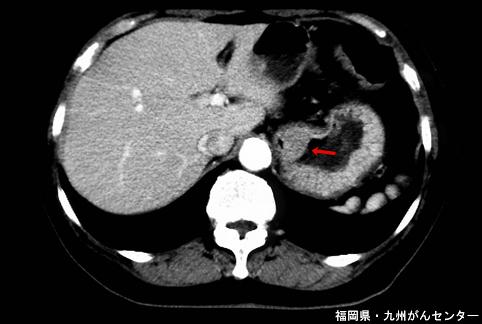

症例提示(所在地,施設名等): 福岡県・ 九州がんセンター

画像ID:5285

[ 画像ID:5285 ]

疾患(病理主体)の分類悪性上皮性腫瘍/未分化癌

部位(臓器別)食道/下

検査方法CT

腫瘍の肉眼分類1型(腫瘤型)/

病変の最大径(ミリ)30〜34

腫瘍の深達度mp